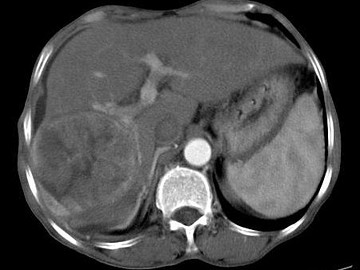

女,40岁,有口服避孕药史,肝区疼痛、腹部包块,AFP阴性,CT扫描如图,最可能的诊断是()

• A.肝细胞腺瘤

• B.肝再生结节

• C.结节性肝癌

• D.肝右叶巨块型肝癌

• E.肝黄色肉芽肿